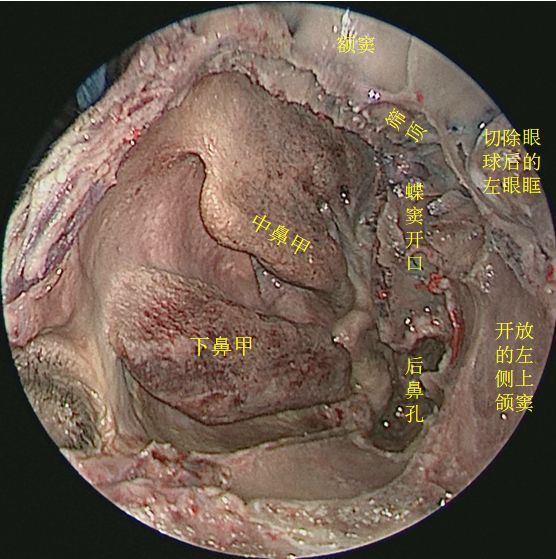

↑ 去除鼻中隔、左侧鼻腔侧壁结构及左眶内容物,前方观察各副鼻窦位置毗邻

去除左侧筛窦、左眶内容物,开放左侧额窦,观察额窦开口

开放左侧额窦前壁,观察额窦腔